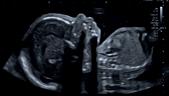

Een echografische afbeelding van een foetus tijdens het tweede trimester SEO onderzoek. Ook hier dragen hoogwaardige beeldkwaliteit en snelheid van het systeem bij aan het stellen van een betrouwbare diagnose.

Canon Medical Systems Nederland helpt u uw doelen te behalen. Wij zijn gespecialiseerd in het ontzorgen van al uw verplichtingen rondom uw Women’s Healthcare echografiesysteem. Zo heeft u meer tijd om optimale zorg te leveren aan uw patiënten.

U scant – Wij doen de rest!